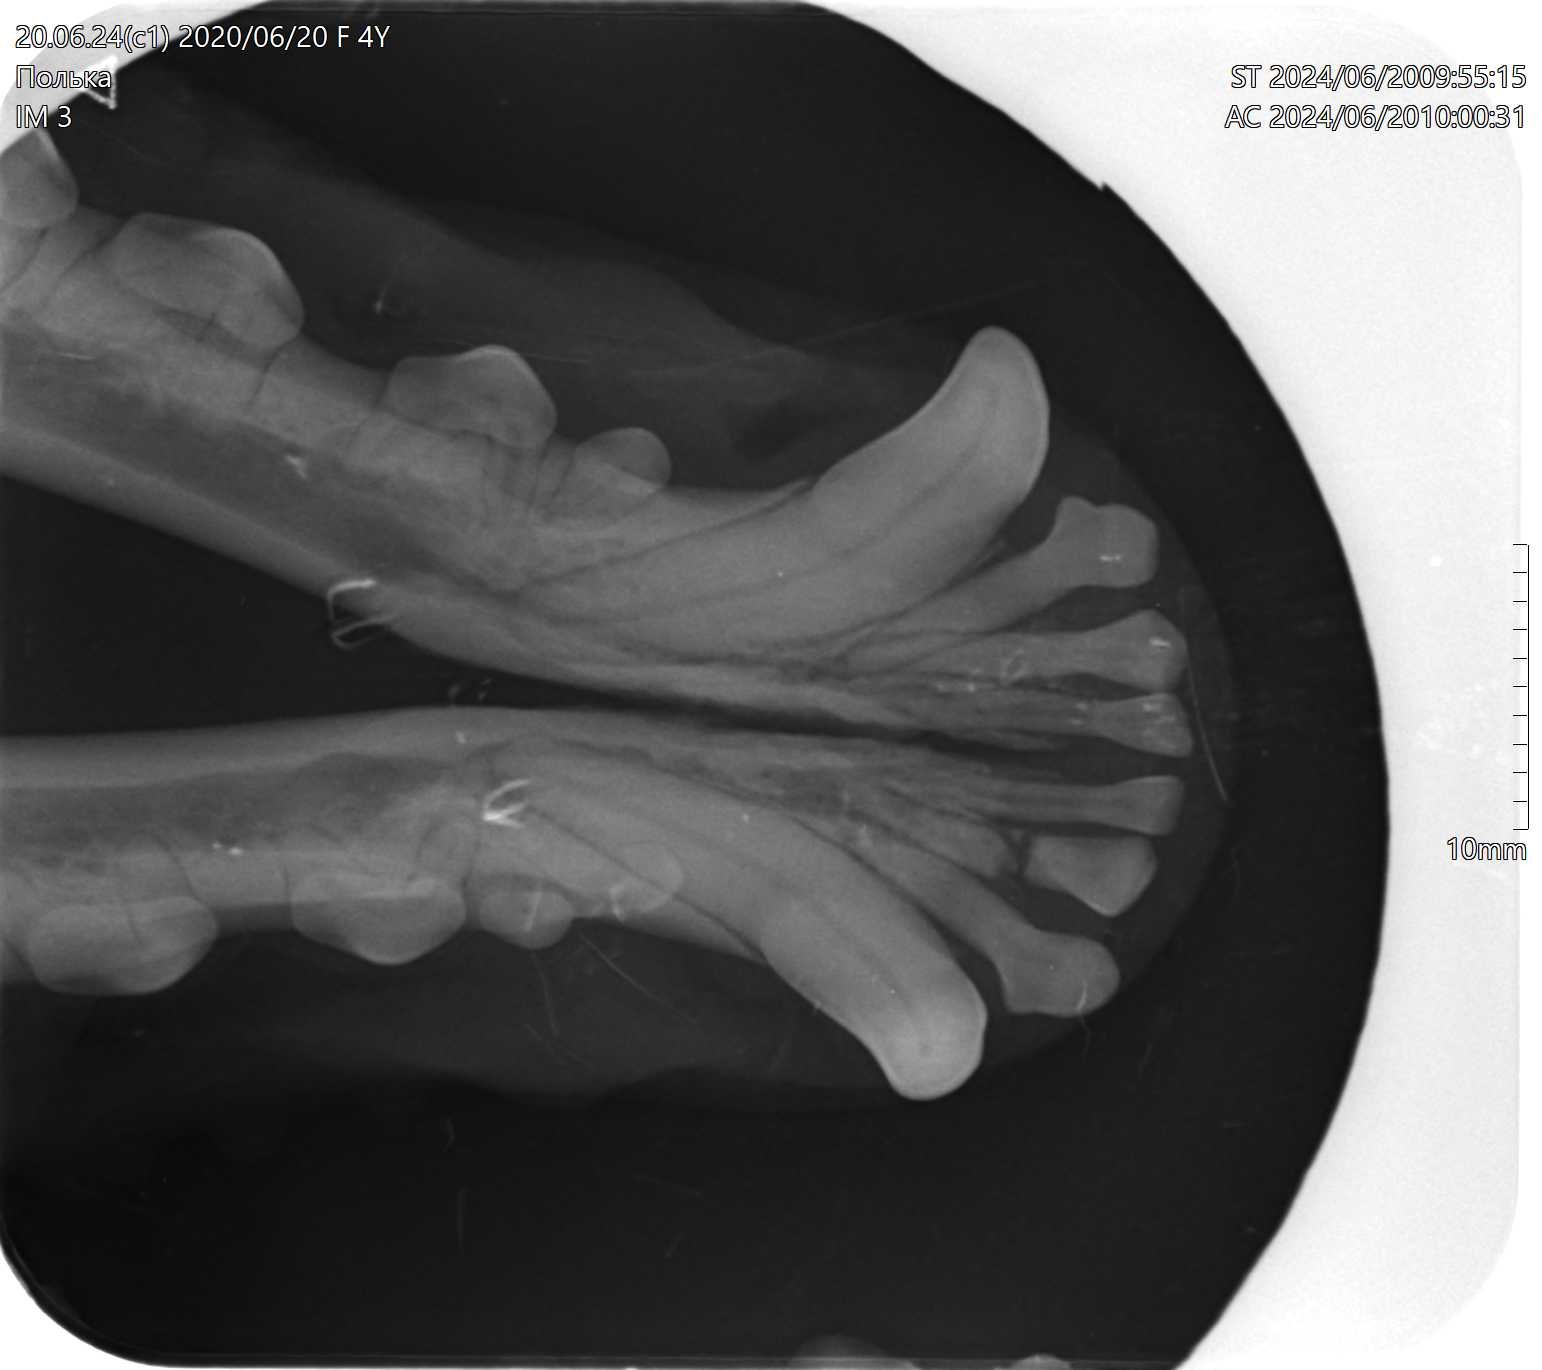

Персистирующие временные зубы у годовалого йоркширского терьера